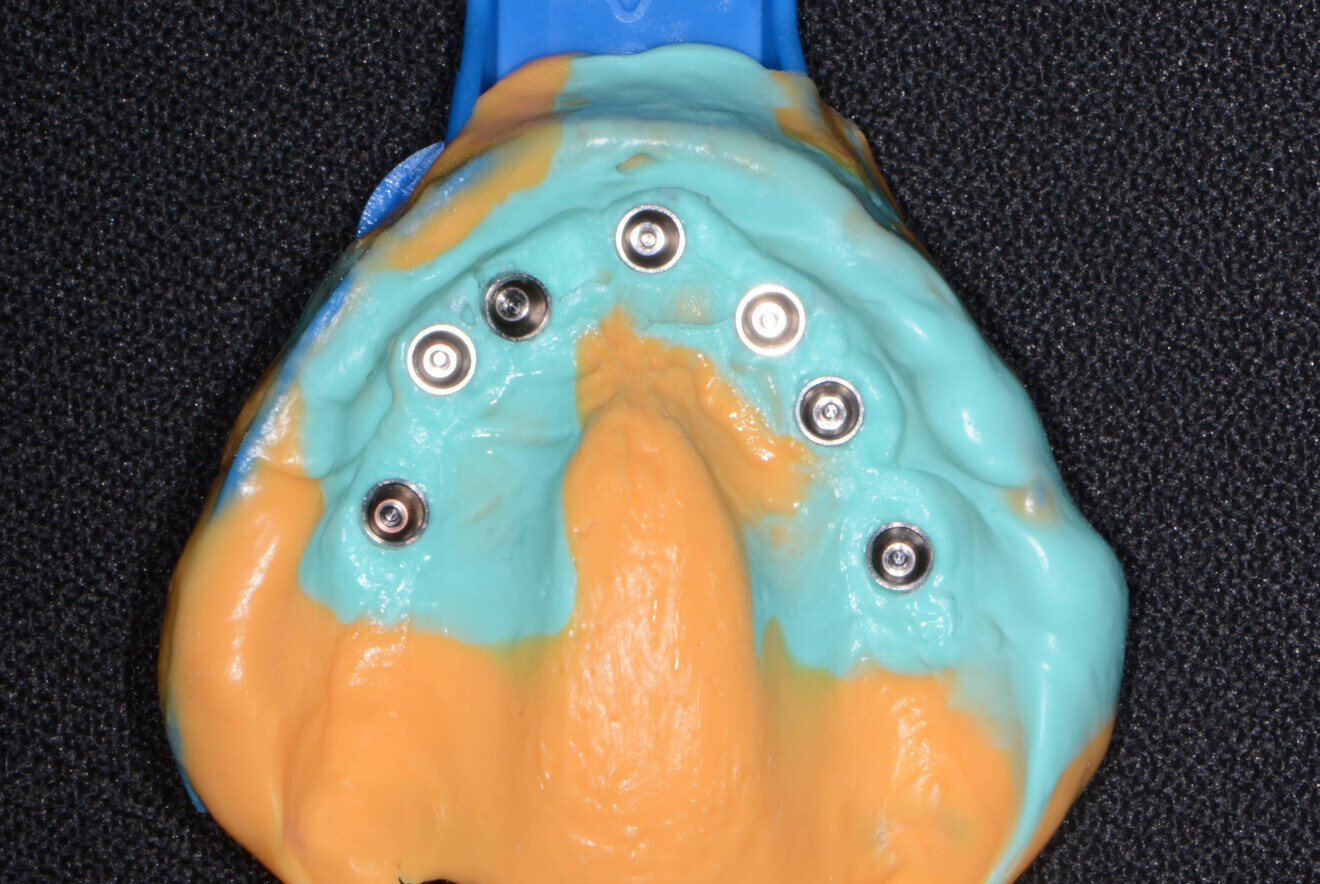

Four months later, the patient presented for impressions for the definitive restoration. Using a heavy- and light-bodied polyvinylsiloxane material (Panasil, Kettenbach) in a stock tray, an open-tray impression was taken of the maxillary arch using transmucosal impression posts (Adin Dental Implant Systems; Figs. 13 & 14). From this impression, the dental laboratory fabricated a PMMA try-in of the proposed maxillary restoration for try-in and evaluation.

Fig. 14: Open-tray impression.